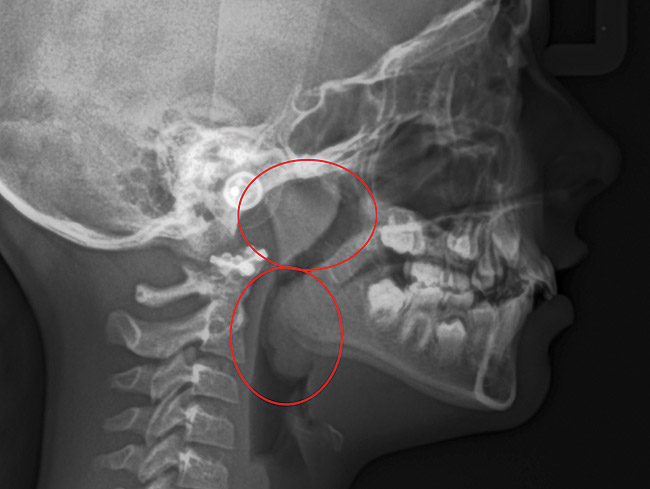

(13.) Seven-year-old brachyfacial child with high body mass index (Case courtesy of James Awbrey, DMD).

Figure 13

(14.) Angle Class III occlusion with constricted maxilla.

Figure 14

(15.) Cephalometric evaluation demonstrates significant tonsillar blockage of the airway and bimaxillary retursion.

Figure 15